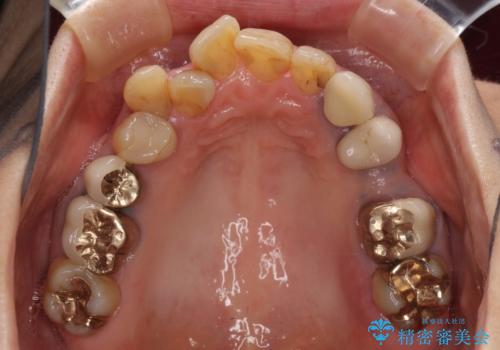

- 奥歯が痛いことを主訴にご来院された患者様です。入院してしまい、治療を2年間放置してしまったとのことでした。

左上は、抜歯とブリッジ治療を行いました(抜歯前に医師と対診)。

左下は、現在も抗がん治療を続けているため、観血的処置(インプラントなどの外科)はなるべく避けたいとのことで入れ歯を希望されました。それに伴い、入れ歯を支える歯のクラウンやりかえも行いました。

患者様はインプラント等の外科処置は希望されなかったため、セラミックと義歯で治療を行いました。

義歯を製作する際は、支えとなる歯の治療も同時に行うことで、義歯の製作が容易になります。

今回もそのように製作したところ、適合がよく安定のよい義歯になりました。患者様本人も使っていて全く痛くないとのことで、追加の調整もなく使用して頂いてます。患者様には、大変満足して頂きました。